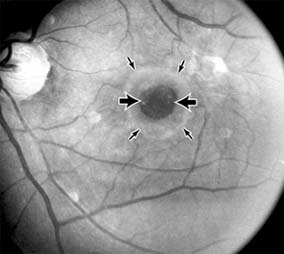

Chapter 10: Retina DISEASES OF THE MACULA AGE-RELATED MACULAR DEGENERATION Age-related macular degeneration is the leading cause of permanent blindness in the elderly. The exact cause is unknown, but the incidence increases with each decade over age 50. Other associations besides age include race (usually Caucasian), sex (slight female predominance), family history, and a history of cigarette smoking. The disease includes a broad spectrum of clinical and pathologic findings that can be classified into two groups: nonexudative ("dry") and exudative ("wet"). Although both types are progressive and usually bilateral, they differ in their manifestations, prognosis, and management. The more severe exudative form accounts for approximately 90% of all cases of legal blindness due to age-related macular degeneration. 1. NONEXUDATIVE MACULAR DEGENERATION Nonexudative age-related macular degeneration is characterized by variable degrees of atrophy and degeneration of the outer retina, retinal pigment epithelium, Bruch's membrane and choriocapillaris. Of the ophthalmoscopically visible changes in the retinal pigment epithelium and Bruch's membrane, drusen are the most typical (Figure 10-1). Drusen are discrete, round, yellow-white deposits of variable size beneath the pigment epithelium and are scattered throughout the macula and posterior pole. With time, they may enlarge, coalesce, calcify, and increase in number. Histopathologically, most drusen consist of focal collections of eosinophilic material lying between the pigment epithelium and Bruch's membrane; they therefore represent focal detachment of the pigment epithelium. In addition to drusen, clumps of pigment irregularly dispersed within depigmented areas of atrophy may progressively appear throughout the macula. The level of associated visual impairment is variable and may be minimal. Fluorescein angiography demonstrates irregular patterns of retinal pigment epithelial hyperplasia and atrophy. Electrophysiologic testing in most patients is normal. There is no generally accepted treatment or means of prevention of this type of macular degeneration. Laser retinal photocoagulation appears to have a beneficial effect on drusen but has not yet been shown to improve visual outcome. Although high plasma levels of antioxidants are associated with a reduced risk of age-related macular degeneration, the use of vitamin supplements does not appear to be preventive. Most patients with macular drusen never experience significant loss of central vision; the atrophic changes may stabilize or progress slowly. However, the exudative stage may develop suddenly at any time, and in addition to regular ophthalmic examinations, patients are given an Amsler grid ( 2. EXUDATIVE MACULAR DEGENERATION Although patients with age-related macular degeneration usually manifest nonexudative changes only, the majority of patients who experience severe vision loss from this disease do so from the development of subretinal neovascularization and related exudative maculopathy. Serous fluid from the underlying choroid can leak through small defects in Bruch's membrane, causing focal detachment of the pigment epithelium. Additional fluid may lead to further separation of the overlying sensory retina, and vision usually decreases if the fovea is involved. Retinal pigment epithelial detachments may spontaneously flatten, with variable visual results, and leave a geographic area of depigmentation at the involved site. Ingrowth of new vessels from the choroid into the subretinal space is the most important change that predisposes patients with drusen to macular detachment and irreversible loss of central vision. These new vessels grow in a flat cartwheel or sea-fan configuration away from their site of entry into the subretinal space. The clinical changes of early subretinal neovascularization are subtle and may be easily overlooked; during this occult stage of new vessel formation, the patient is asymptomatic, and the new vessels may not be apparent either ophthalmoscopically or angiographically. The ophthalmologist must maintain a high index of suspicion that subretinal neovascularization is present whenever a patient with evidence of age-related macular degeneration has sudden or recent central vision loss, including blurred vision, distortion, or a new scotoma. If the fundus examination reveals subretinal blood, exudate, or a grayish-green choroidal lesion in the macula, there is great likelihood that neovascularization is present, and a fluorescein or indocyanine green angiogram should be obtained promptly to determine if a treatable lesion can be identified. Although some subretinal neovascular membranes may spontaneously regress, the natural course of subretinal neovascularization in age-related macular degeneration is toward irreversible loss of central vision over a variable period of time. The sensory retina may be damaged by long-standing edema, detachment, or underlying hemorrhage. Furthermore, a hemorrhagic detachment of the retina may undergo fibrous metaplasia, resulting in an elevated subretinal mass called a disciform scar. This elevated fibrovascular mound of variable size represents the cicatricial end stage of exudative age-related macular degeneration. It is usually centrally located and results in permanent loss of central vision. Treatment In the absence of subretinal neovascularization, no medical or surgical treatment of serous retinal pigment epithelial detachment is of proved benefit. The use of parenteral alpha interferon, for example, has not been effective for this disease. However, if a well-defined extrafoveal ( Krypton laser photocoagulation of juxtafoveal (<200 Following successful photocoagulation of a subretinal neovascular membrane, recurrent neovascularization either contiguous with or remote from the laser scar may occur in one-half of cases by 2 years. Recurrence is often accompanied by severe vision loss, so that careful monitoring with Amsler grids, ophthalmoscopy, and angiography is essential. Low-dose radiotherapy has provided encouraging results in patients with subfoveal neovascularization. Patients with impaired central vision in both eyes may benefit from a variety of low vision aids. CENTRAL SEROUS CHORIORETINOPATHY Central serous chorioretinopathy is characterized by serous detachment of the sensory retina as a consequence of focal leakage of fluid from the choriocapillaris through a defect in the retinal pigment epithelium (Figures 10-2 and 10-3). This disease typically affects young to middle-aged men and may be related to life stress events. Most patients present with the sudden onset of blurred vision, micropsia, metamorphopsia, and central scotoma. Visual acuity is often only moderately decreased and may be improved to near-normal with a small hyperopic correction. The diagnosis is made by slitlamp examination of the fundus; the presence of serous detachment of the sensory retina in the absence of ocular inflammation, subretinal neovascularization, an optic pit, or a choroidal tumor is diagnostic. The retinal pigment epithelial lesion appears as a small, round or oval, yellowish-gray spot that is variable in size and may be difficult to detect without the aid of fluorescein angiography. Fluorescein dye leaking from the choriocapillaris may accumulate below the pigment epithelium or sensory retina, resulting in a variety of patterns including the well-recognized smokestack configuration. Approximately 80% of eyes with central serous chorioretinopathy undergo spontaneous resorption of subretinal fluid and recovery of normal visual acuity within 6 months after the onset of symptoms. Despite normal acuity, however, many patients have a mild permanent visual defect, such as a decrease in color sensitivity, micropsia, or relative scotoma. Twenty to 30 percent of patients will have one or more recurrences of the disease, and complications-including subretinal neovascularization and chronic cystoid macular edema-have been described in patients with frequent and prolonged serous detachments. The cause of central serous chorioretinopathy is unknown; there is no convincing evidence that the disease is either infectious or due to retinal pigment epithelial dystrophy. Argon laser photocoagulation directed to the active leak significantly shortens the duration of the sensory detachment and hastens the recovery of central vision, but there is no evidence that prompt photocoagulation reduces the chance of permanent loss of visual function. Although the complications of retinal laser photocoagulation are few, it is probably not advisable to recommend immediate photocoagulation treatment in all patients with central serous chorioretinopathy. The duration and location of disease, the condition of the fellow eye, and occupational visual requirements are all considerations upon which treatment decisions are based. MACULAR EDEMA Retinal edema involving the macula may be associated with a variety of intraocular inflammatory diseases, retinal vascular diseases, intraocular surgery, inherited or acquired retinal degenerations, medications, macular membranes, or unknown causes. Macular edema may be diffuse, with nonlocalized intraretinal fluid causing thickening of the macula. When edema fluid accumulates in honeycomb-like spaces of the outer plexiform and inner nuclear layers, it is called cystoid macular edema. On fluorescein angiography, fluorescein dye leaks from the perifoveal retinal capillaries and accumulates in a flower-petal pattern about the fovea (Figure 10-4). The most widely recognized association with cystoid macular edema is intraocular surgery. Approximately 50% of eyes undergoing uneventful intracapsular cataract extraction and 20% of eyes undergoing extracapsular cataract extraction develop angiographic cystoid macular edema. Clinically significant edema usually occurs within 4-12 weeks postoperatively, but in some instances its onset may be delayed for months or years. Many patients with cystoid macular edema of less than 6 months' duration have self-limited leakage that will resolve without treatment. Topical or local (or both) anti-inflammatory therapy may be of value in restoring visual acuity in some patients with chronic postoperative macular edema. YAG laser vitreolysis (see Chapter 24) and surgical vitrectomy may be of benefit when the macular edema is associated with vitreous tissue incarcerated in the cataract wound or adherent to anterior segment structures. When an intraocular lens implant is the cause of postoperative macular edema due to its design, positioning, or inadequate fixation, removal of the lens implant can be considered. INFLAMMATORY DISORDERS INVOLVING THE MACULA Presumed Ocular Histoplasmosis Syndrome (Figures 10-5, 10-6 and 10-7) In this disease, serous and hemorrhagic detachments of the macula are associated with multiple peripheral atrophic chorioretinal scars and peripapillary chorioretinal scarring (see Chapter 7). The syndrome usually occurs in healthy patients between the third and sixth decades of life, and the scars are probably caused by an antecedent subclinical systemic infection with Histoplasma capsulatum. The macular detachments are due to subretinal neovascularization, and the visual prognosis depends on the proximity of the neovascular membrane to the center of the fovea. If the membrane extends inside the foveal avascular zone, only 15% of eyes will retain 20/40 vision. A macular scar may change over time, and 10% of patients with normal maculae will develop new atrophic scars in this region. The relative risk of developing macular subretinal neovascularization in the second eye of an affected patient is significant, and these patients should be instructed in the frequent use of the Amsler grid and the importance of prompt examination when changes are detected. Argon laser photocoagulation of a subretinal neovascular membrane outside the foveal avascular zone in symptomatic patients is of value in preventing severe vision loss. The surgical removal of submacular membranes may prove useful in preserving vision. Acute Multifocal Posterior Placoid Pigment Epitheliopathy (AMPPPE) AMPPPE typically affects healthy young patients who develop rapidly progressive bilateral vision loss in association with ophthalmoscopically visible multifocal flat gray-white subretinal lesions involving the pigment epithelium (Figure 10-8). The cause of this disease, which in many instances is associated with evidence of an influenza-like illness, is unknown; the course and nature of the illness suggests the possibility of viral infection. The characteristic feature of the disease is the rapid resolution of the fundus lesions and a delayed return of visual acuity to near-normal levels. Although the prognosis for visual recovery in this acute self-limited disease is good, many patients will identify small residual paracentral scotomas when carefully tested. Extensive pigmentary changes remaining during the late stages of AMPPPE may mimic widespread retinal degeneration; the clinical history and normal electrophysiologic findings aid in this differential diagnosis. Geographic Helicoid Peripapillary Choroidopathy This is a chronic progressive and recurrent multifocal inflammatory disease of the retinal pigment epithelium, choriocapillaris, and choroid. It characteristically involves the juxtapapillary retina and extends radially to involve the macula and peripheral retina. The active stage manifests itself as sharply demarcated gray-yellow lesions with irregular borders that appear to involve the pigment epithelium and choriocapillaris. Vitritis, anterior uveitis, and subretinal neovascularization have been associated with this disorder. Involvement is usually bilateral, and the cause is unknown. The natural history of this indolent inflammatory disease is variable and may correlate with the presence of disease in the fellow eye. Local or systemic corticosteroid treatment may be of benefit when active inflammation is present; laser photocoagulation is administered as indicated for the complication of subretinal neovascularization. Vitiliginous Chorioretinitis (Birdshot Retinochoroidopathy) This is a syndrome characterized by diffuse cream-colored patches at the level of the pigment epithelium and choroid, retinal vasculitis associated with cystoid macular edema, and vitritis. The associations with HLA-A29 and with retinal S-antigen suggest that this disease has a genetic predisposition and that retinal autoimmunity plays a role in its manifestations. In many cases, electroretinography, electro-oculography, and dark adaptation studies are abnormal. The course of the disease is that of exacerbation and remission with variable visual outcomes; visual loss has been attributed to chronic cystoid macular edema, optic atrophy, macular scarring, or subretinal neovascularization. Corticosteroid therapy has not proved effective against this disease. Acute Macular Neuroretinopathy Acute macular neuroretinopathy is characterized by the acute onset of paracentral scotomas and mild visual acuity loss accompanied by wedge-shaped parafoveal retinal lesions in the deep sensory retina of one or both eyes. The macular lesions are subtle, reddish-brown, and best seen with a red-free light. The patients are usually young adults with a history of acute viral illness. While the retinal lesions may fade, the scotomas tend to persist and remain symptomatic. Multiple Evanescent White Dot Syndrome This is an acute and self-limited unilateral disease that affects mainly young women and is characterized clinically by multiple white dots at the level of the pigment epithelium, vitreal cells, and transient electroretinographic abnormalities. The cause is unknown. There is no evidence of associated systemic disease. The retinal lesions gradually regress in a matter of weeks, leaving only minor retinal pigment epithelial defects. ANGIOID STREAKS Angioid streaks appear as irregular, jagged tapering lines that radiate from the peripapillary retina into the macula and peripheral fundus (Figure 10-9). The streaks represent linear crack-like dehiscences in Bruch's membrane. The lesions are rarely noted in children and probably develop in the second or third decade of life. Early in the disease the streaks are sharply outlined and red-orange or brown. Subsequent fibrovascular tissue growth may partially or totally obscure the streak margins. Nearly 50% of patients with angioid streaks have an associated systemic disease. Pseudoxanthoma elasticum, Paget's disease of bone, Ehlers-Danlos syndrome, and several hemoglobinopathies and hemolytic disorders have been associated with this retinal disease, but the most common association is with age-related degeneration of Bruch's membrane. Patients with angioid streaks should be warned of the potential risk of choroidal rupture from even relatively mild eye trauma. Older patients with the disease are at risk of developing serous and hemorrhagic detachments of the retina as a consequence of subretinal neovascularization. Laser treatment may be used to photocoagulate extrafoveal neovascular membranes; however, other neovascular membranes are likely to occur. Prophylactic treatment of angioid streaks before subretinal neovascularization develops is not recommended. MYOPIC MACULAR DEGENERATION Pathologic myopia is one of the leading causes of blindness in the United States and is characterized by progressive elongation of the eye with subsequent thinning and atrophy of the choroid and pigment epithelium in the macula. Peripapillary chorioretinal atrophy and linear breaks in Bruch's membrane ("lacquer cracks") are characteristic findings on ophthalmoscopy (Figure 10-10). The degenerative changes of the macular pigment epithelium resemble those found in the older patient with age-related macular degeneration. A characteristic lesion of this disease is a raised, circular, pigmented macular lesion called a Fuchs spot. Most patients are in the fifth decade when the degenerative macular changes cause a slowly progressive loss of vision; rapid loss of visual acuity is usually caused by serous and hemorrhagic macular degeneration overlying a subretinal neovascular membrane. Fluorescein angiography in patients with pathologic myopia may show delayed filling of choroidal and retinal blood vessels. Angiography is helpful in identifying and locating the site of subretinal neovascularization in patients who develop serous or hemorrhagic detachments of the macula. Because of the frequent close proximity of the subretinal neovascular membrane to the foveola in these patients, laser photocoagulation may not be possible. As subretinal neovascular membranes tend to remain small and because photocoagulation-associated chorioretinal atrophy tends to progress in patients with pathologic myopia, retinal laser treatment is not as beneficial as in other diseases associated with macular subretinal neovascularization. The chorioretinal changes of pathologic myopia predispose the retina to breaks and thus to retinal detachment. Peripheral retinal findings may include paving stone degeneration, pigmentary degeneration, and lattice degeneration. Retinal breaks usually occur in areas involved with chorioretinal lesions, but they also arise in areas of apparently normal retina. Some of these breaks, particularly those of the "horseshoe" and round retinal tear type, will progress to rhegmatogenous retinal detachment. MACULAR HOLE A macular hole is a partial or full-thickness absence of the sensory retina in the macula. This disorder occurs most often in elderly women and is associated with elevated plasma fibrinogen levels. The typical finding on biomicroscopy of the symptomatic eye is a full-thickness, round or oval, sharply defined hole measuring one-third disk diameter in the center of the macula, which may be surrounded by a ring detachment of the sensory retina (Figure 10-11). With a full-thickness macular hole, visual acuity is impaired and metamorphopsia, as well as a central scotoma, are present on the Amsler grid. An operculum of retinal tissue may overlie the macular hole. Tangential traction from epiretinal vitreous cortex plays an important role in the pathogenesis of macular hole. Early stages of macular hole formation, such as a deep foveal yellow spot or ring, may be reversible as the posterior vitreous cortex spontaneously separates from the retina. Therapy for macular hole disease involves reattaching and potentially restoring function to the retina overlying the cuff of subretinal fluid surrounding the hole. While the anatomic results of vitrectomy surgery to close macular holes are encouraging, the clinical benefits are still under study. EPIRETINAL MACULAR MEMBRANES Fibrocellular membranes may proliferate on the surface of the retina, either in the macula or peripheral retina. Contraction or shrinkage of these epiretinal membranes may cause varying degrees of visual distortion, intraretinal edema, and degeneration of the underlying retina. Biomicroscopy usually shows retinal wrinkles and vessel tortuosity and may rarely also show retinal hemorrhages, cotton-wool spots, serous retinal detachment, and macular hole; a posterior vitreous detachment is nearly always present (Figure 10-12). Disorders associated with epiretinal membranes include retinal tears with or without rhegmatogenous retinal detachment, vitreous inflammatory diseases, trauma, and a variety of retinal vascular diseases. Patients with macular distortion and vision loss caused by epiretinal membrane contraction are usually left with stable visual acuity, suggesting that membrane contraction is a short-lived and self-limited process. Surgical peeling of severe epiretinal membranes can be performed successfully, but regrowth of epiretinal tissues occurs in some cases. There is no role for photocoagulation in the treatment of epiretinal macular membrane disease. TRAUMATIC MACULOPATHY Blunt trauma to the anterior segment of the eye may cause a contrecoup injury to the retina called commotio retinae. The retina develops a gray-white color that affects primarily the outer retina and may be confined to the macular area (Berlin's edema) or may involve extensive areas of the peripheral retina. The retinal whitening in the macular area may clear completely, or impairment of central vision may be permanent and associated with a pigmented retinal scar (Figure 10-13) or a macular hole. Trauma similar to that which causes Berlin's edema may also cause choroidal rupture with subretinal hemorrhage and permanent central vision loss. In addition to blunt trauma, several other traumatic injuries involving the macula are of importance. Purtscher's retinopathy is characterized by multiple patches of superficial retinal whitening and retinal hemorrhages in each eye of a patient after severe compression injury to the head or trunk. Terson's syndrome is seen in approximately 20% of patients after traumatic (or spontaneous) subarachnoid or subdural hemorrhage and is characterized by vitreous and superficial macular hemorrhage. Solar retinopathy refers to a specific foveolar lesion that occurs after sun-gazing and is best described as a usually bilateral sharply circumscribed and often irregularly shaped partial-thickness hole or depression in the center of the fovea. MACULAR DYSTROPHIES Macular dystrophies differ from degenerations in that the former are inherited, though not necessarily evident at birth, and are not associated with systemic diseases. Most often the disorder is restricted to the macula; it may be symmetric or asymmetric, but eventually both eyes are affected. In the early stages of some of these disorders the visual acuity may be reduced while the macular changes are subtle or absent on ophthalmoscopy, and the patient's complaint may be dismissed as spurious. Conversely, in other macular dystrophies, the ophthalmoscopic changes may be very striking at a time when the patient is free of visual symptoms. One method of classifying the more common macular dystrophies is to consider the presumptive anatomic layer or layers of the retina involved (Table 10-1). X-Linked Juvenile Retinoschisis This is a congenital disease of males characterized by a macular lesion called "foveal schisis." On slitlamp examination, foveal schisis appears as small superficial retinal cysts arranged in a stellate pattern accompanied by radial striae centered in the foveal area (Figure 10-14). Visual acuity is usually between 20/40 and 20/200; peripheral visual field abnormalities are present in the 50% of patients with associated peripheral retinoschisis. The posterior pole appears normal on fluorescein angiography, and this may be helpful in the clinical differentiation from cystoid macular edema. B wave abnormalities on the electroretinogram are consistent with the histopathologic finding of intraretinal splitting in the nerve fiber layer. Cone-Rod Dystrophies The cone-rod dystrophies constitute a relatively rare group of disorders that may be regarded as a single entity showing variable expressivity. Most cases are sporadic, but familial cases are usually transmitted by an autosomal dominant inheritance pattern. Cone-rod dystrophy is characterized by predominant involvement of the cone photoreceptors with progressive color vision defects and associated loss of visual acuity. A bilateral and symmetric bulls-eye pattern of depigmentation and a corresponding zone of hyperfluorescence surrounding a central nonfluorescent spot (similar to that seen in chloroquine retinopathy) are the most commonly described biomicroscopic and angiographic changes in these patients (Figure 10-15). As the disease progresses, the electroretinogram shows marked loss of cone function associated with a slight to moderate loss of rod function. Histopathologic study shows absence of macular and paramacular photoreceptors, and there is associated pigment epithelium degeneration. Fundus Albipunctatus Fundus albipunctatus is an autosomal recessive nonprogressive dystrophy characterized by a myriad of discrete small white dots at the level of the pigment epithelium sprinkled about the posterior pole and midperiphery of the retina. Patients are night-blind with normal visual acuity, normal visual fields, and normal color vision. While the electroretinogram and electro-oculogram are usually normal, dark adaptation thresholds are markedly elevated. Retinitis punctata albescens is the less common progressive variant of this dystrophy. Fundus Flavimaculatus (Stargardt's Disease) This is a bilateral and symmetric autosomal recessive disorder characterized by multiple yellow-white fleck lesions of variable size and shape confined to the retinal pigment epithelium (Figure 10-16). Many patients suffer central visual loss in childhood; however, macular involvement and the ultimate visual outcome are variable. Fluorescein angiography is important in differentiating flecks from drusen; the former are usually hypofluorescent. The electroretinogram and electro-oculogram are usually normal. Histopathologic abnormalities are confined to the pigment epithelium; the yellow flecks seen clinically are dense accumulations of lipofuscin within engorged pigment epithelial cells. Vitelliform Dystrophy (Best's Disease) Vitelliform dystrophy is an autosomal dominant disorder with variable penetrance and expressivity with onset usually in childhood. The ophthalmoscopic appearance is variable and ranges from a mild pigmentary disturbance within the fovea to the typical vitelliform or "egg yoke" lesion located within the central macula (Figure 10-17). This characteristic cyst-like lesion is generally quite round and well demarcated and contains homogeneous opaque yellow material lying at the apparent level of the retinal pigment epithelium. The "egg yoke" may degenerate and be associated with subretinal neovascularization, subretinal hemorrhage, and extensive macular scarring. Visual acuity often remains good, and the electroretinogram is normal; the distinctly abnormal electro-oculogram is the hallmark of this disease. PREVIOUS | NEXT Page: 1 | 2 | 3 | 4 | 5 | 6 | 7 | 8 | 9 10.1036/1535-8860.ch10 |